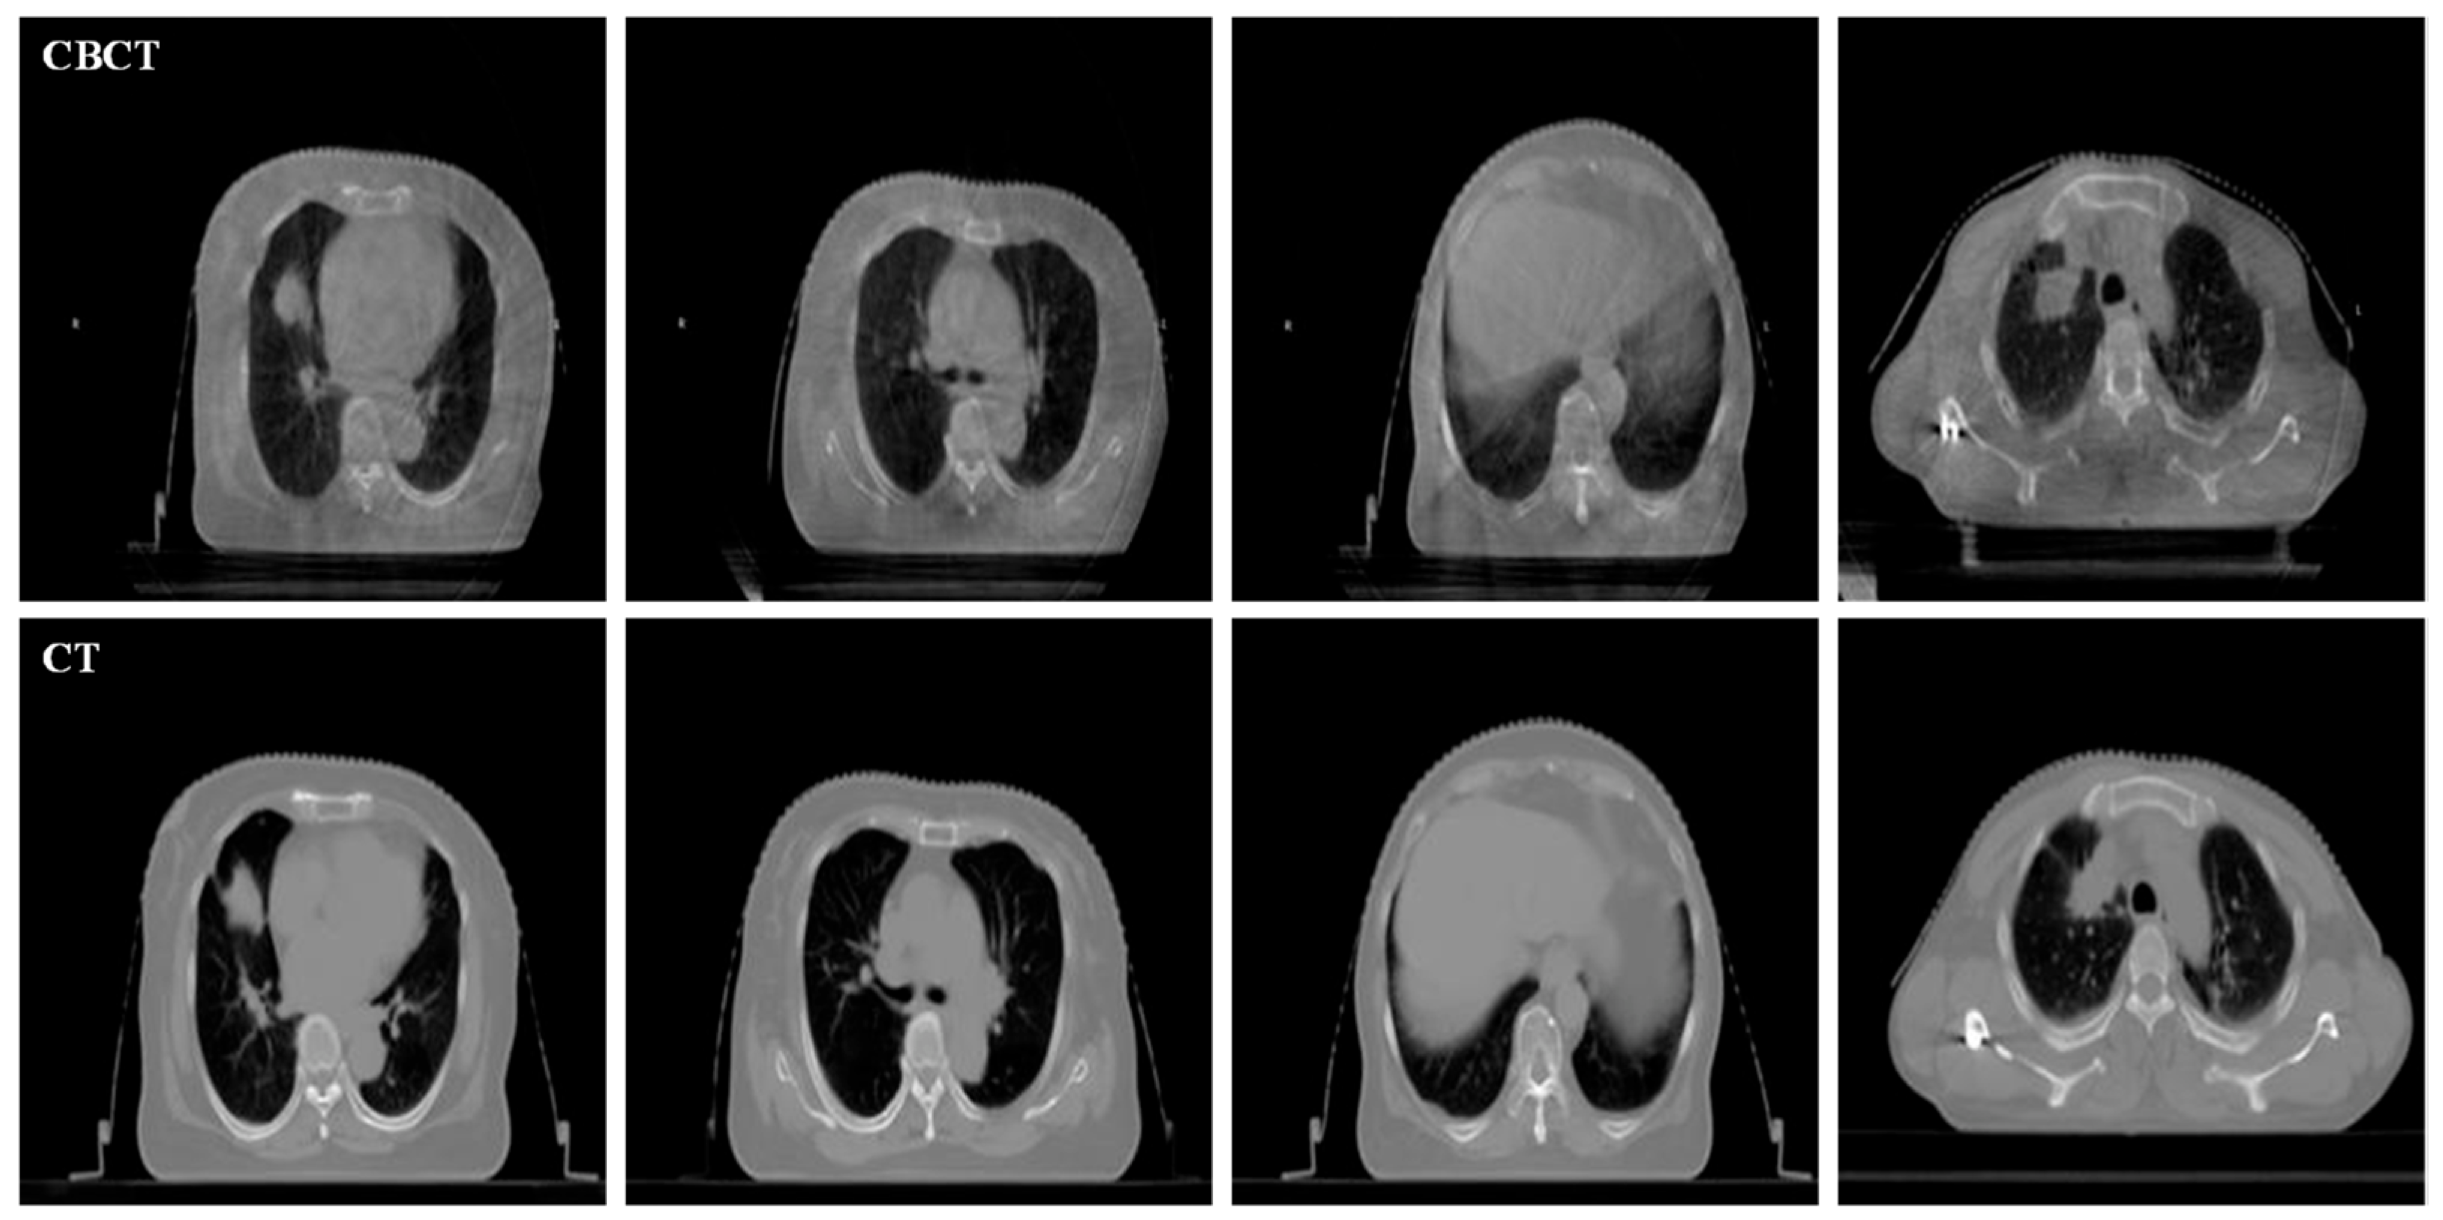

As shown in Figure 1, CBCT images usually have low contrast and visual quality due to their small imaging dose compared with CT images. Compared with CT, CBCT has a small imaging dose, which means that its imaging is more susceptible to interference from environments such as a strong magnetic field, resulting in more noise in the CBCT image. The degradation of CBCT will reduce image contrast and increase the ambiguity of structures of important regions, which makes it unable to play its due role in IGRT [11]. Huang et al. proved that the accuracy of radiotherapy can be improved by using CBCT enhancement technology in IGRT [12]. Thus, it has become a new research topic to use image enhancement technology to improve the quality of CBCT.

Figure 1.

Examples of unregistered CBCT (the first row) and CT (the second row) images.